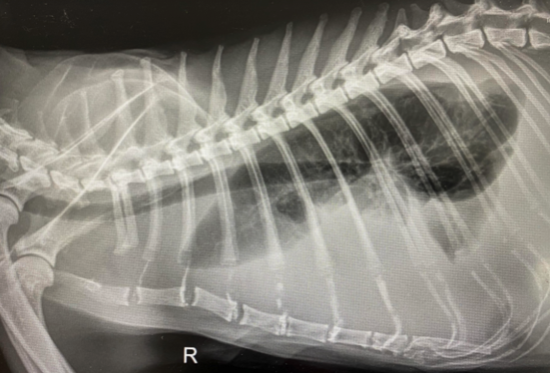

Radiographs

The diagnostic report from the thoracic radiographs stated severe pleural effusion in pleural cavity, which means in the space between the chest wall and the heart and lungs there was a large amount of free fluid present. In the abdomen there was poor serosal detail with small amounts of stool in the colon.

The pleural effusion is indicative of the radiopaque (uniformly white color) surrounding the lungs that show up as radiolucent (dark).

- Radiographs of right lateral thoracic view. [Digital image]. (2021). Retrieved June 24, 2021 from IVS Emergency Hospital.